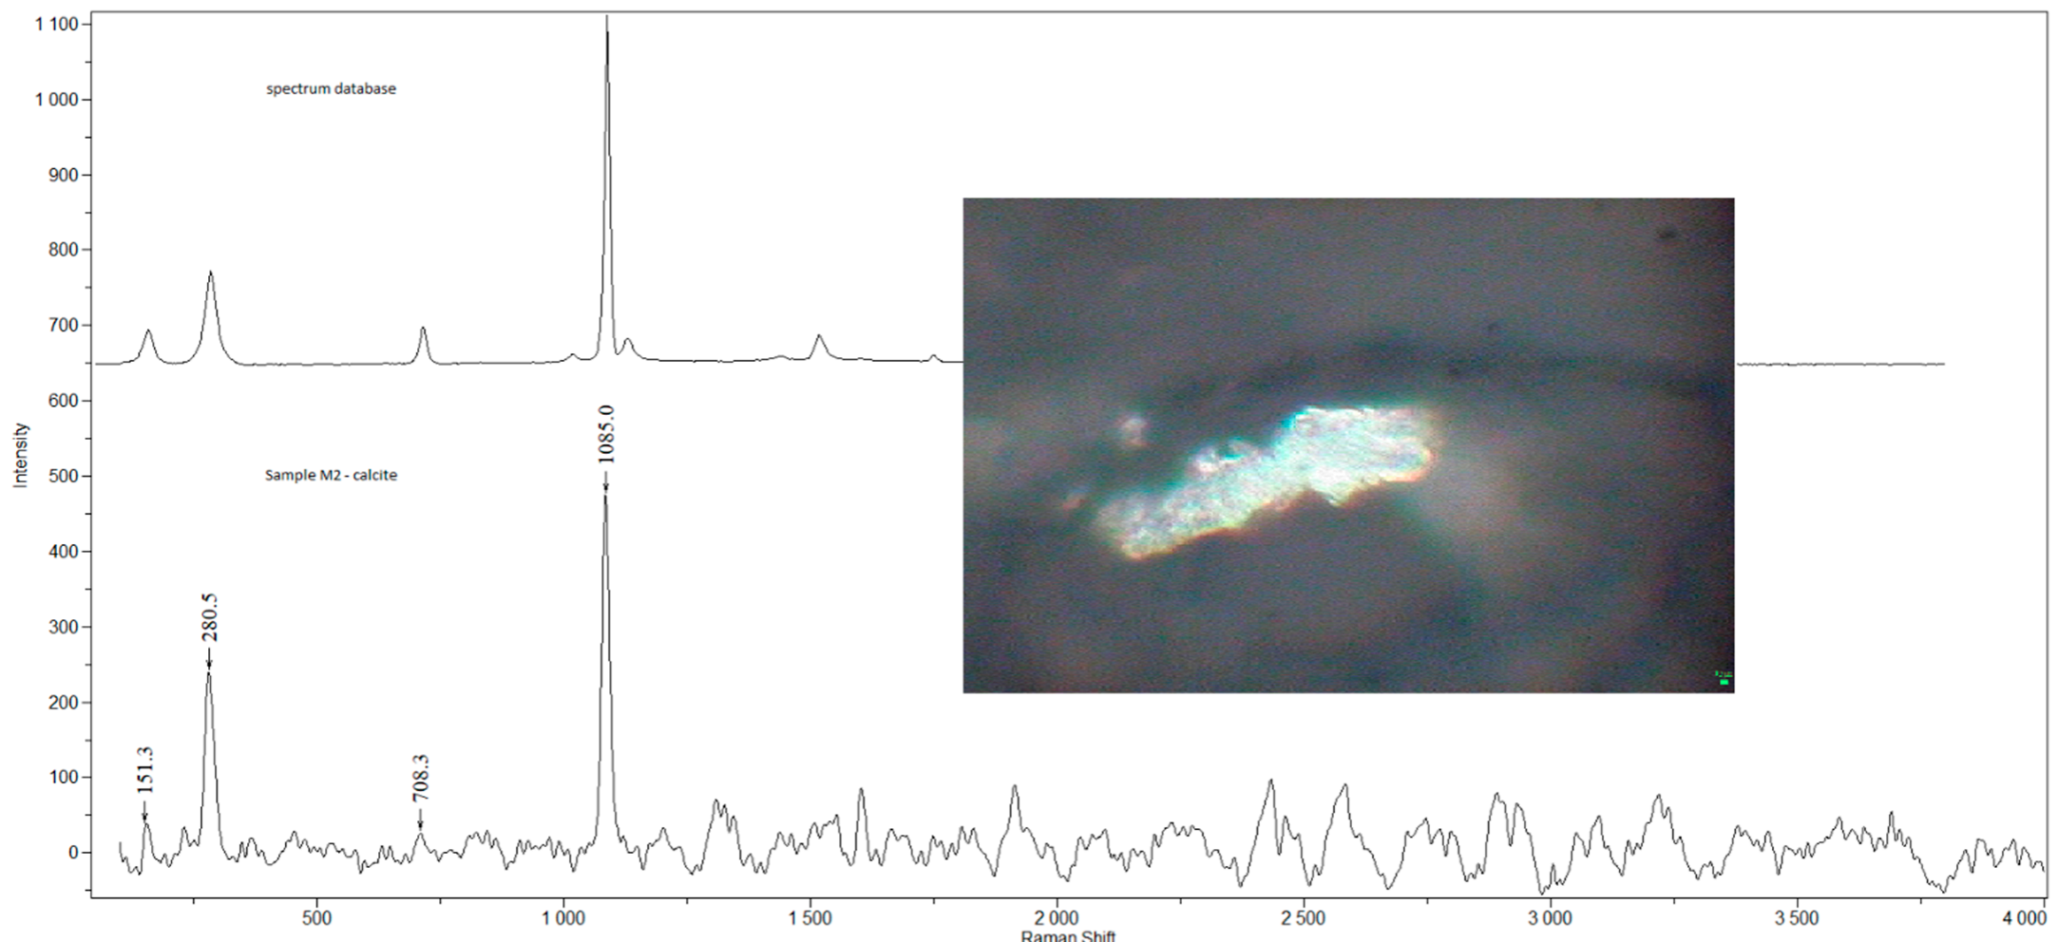

2.2. Raman Microspectroscopy

3.1. Detected Compounds

| M3 | m | 38 | N | welder (M) | AC, CaSO4, Fe3O4, GR, TiO2-A | 1 |